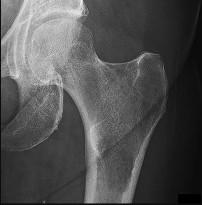

A 28-year-old male sustains a high-energy Pauwels type III femoral neck fracture.

Compared to a Pauwels type I fracture, which of the following biomechanical forces is most significantly increased at the fracture site?

Explanation

The Pauwels classification of femoral neck fractures is based on the angle of the fracture line relative to the horizontal plane. A type III fracture has an angle greater than 50 degrees, making it more vertically oriented. This vertical orientation significantly increases shear forces across the fracture site, leading to a higher risk of varus collapse, nonunion, and fixation failure.